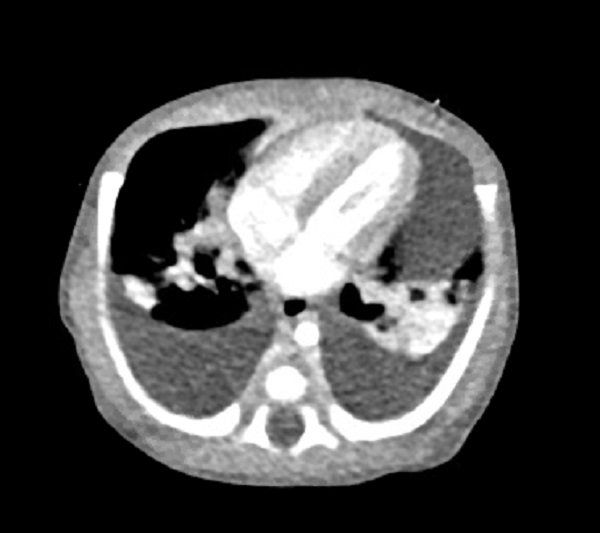

Physical examination in the NICU showed a 3.4kg patient with a temperature of 98.3F, heart rate 163, respiratory rate 53, blood pressure 88/56 and oxygen saturation of 88% on 10 liters. Patient showed increased work of breathing with diminished breath sounds, bilaterally. Rapid PCR for influenza A, influenza B, RSV and COVID-19 were negative. Echocardiogram showed normal heart function with pleural effusions. Similarly, chest ultrasound showed evidence of bilateral pleural effusions. The decision was made to perform a CT scan of the patient’s head and chest to further evaluate pleural effusions and xanthochromia noted on lumbar puncture. Patient had a normal head CT. Chest CT scan showed multifocal lung opacities consistent with inflammation and bilateral moderate-sized pleural effusions greater on the left than right (Fig. 2). Bilateral chest tubes were placed. Upon placement the left side drained ~55cc Chylous fluid, and the right side drained <5cc Chylous fluid. Pleural fluid analysis showed glucose 63, protein 3.2, LDH 135, and a triglyceride level. Due to negative infectious workout bronchoalveolar lavage (BAL) was suggested, however chylothorax was high on the differential.

Figure 2

CT scan showing bilateral pleural effusion.